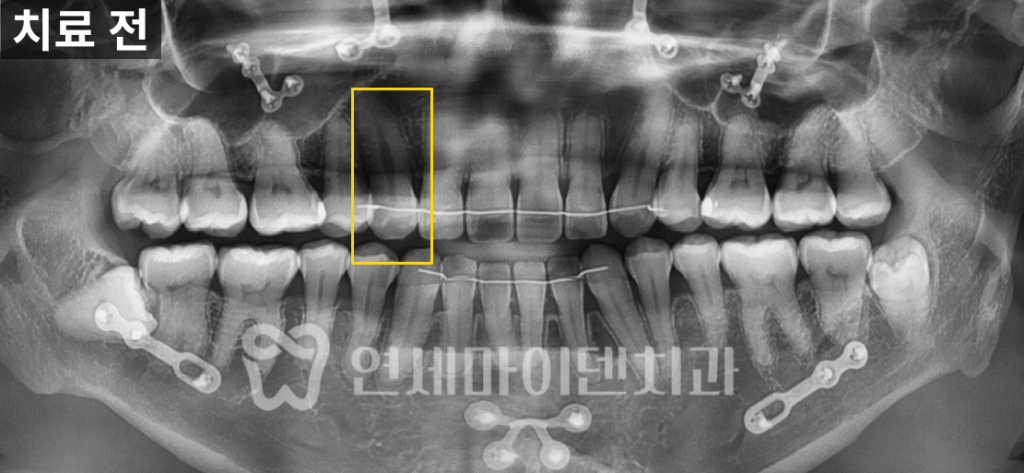

오늘 사례의 환자분은 치아가 분홍빛으로

검게 변색됐다는 주소로 병원을 찾으셨습니다.

앞니 바로 옆에 위치한 치아인데 옆 치아와 색이 확연히 다른 것을 볼 수 있습니다.

이 환자분도 이전 치과에서 교정과 양악수술을 하셔서

확실하지는 않지만, 후자의 경우를 의심해볼 수 있었습니다.